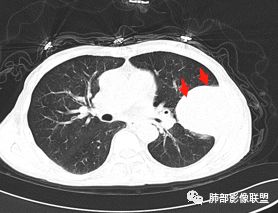

老年男性,外伤入院,“左上肺”实性肿块,边缘光滑,突破壁层胸膜并侵犯肋骨及肋间肌,增强扫描轻度强化,可见明显坏死。

• 胸CT:左肺上叶实性占位,病灶与支气管无关,病灶对斜裂挤压,病灶周围光滑,未见分叶、毛刺;纵隔窗可见病灶内低密度区,病灶对胸壁侵袭,并可见肋骨破坏。

胸CT:左上肺实性大肿块,边缘光滑,突破胸膜侵犯肋骨及肋间肌,纵隔淋巴结肿大,增强呈轻度强化,可见明显片状坏死。